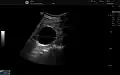

The complex cyst can be further evaluated with doppler ultrasonography, and for Bosniak classification and follow-up of complex cysts, either contrast-enhanced ultrasound (CEUS) or contrast CT is used.[13]

Renal cyst as seen on abdominal ultrasound -

A very small (8 mm) simple renal cyst. -